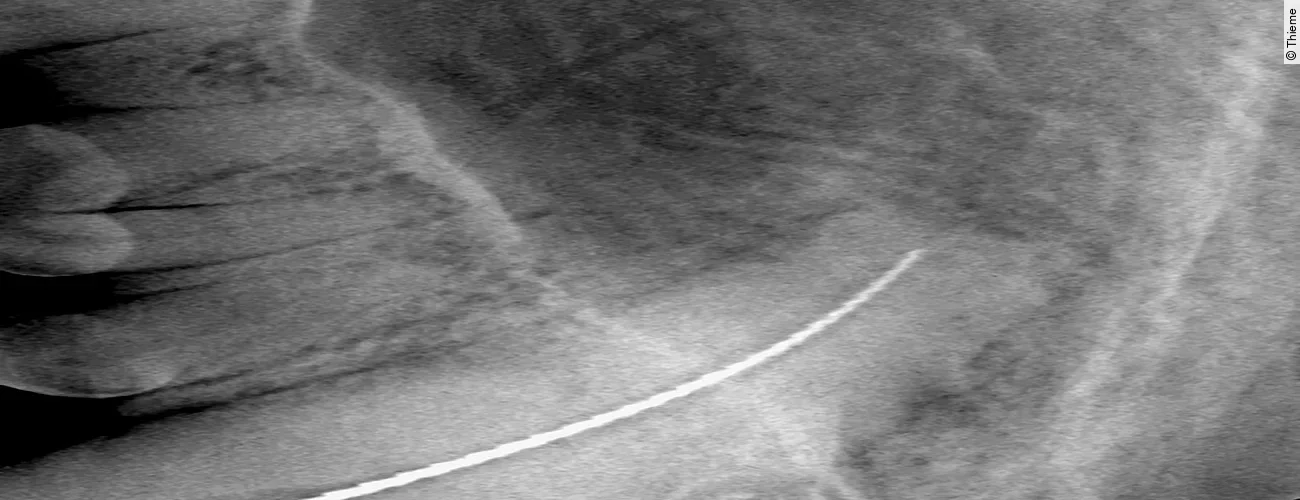

Replantation nach Avulsion Oberkieferfangzahn rechts

Der Originalartikel „Avulsion Oberkieferfangzahn rechts“ stammt aus dem Bild-Atlas der Zahnbehandlungen Hund und Katze; 2. aktualisierte Auflage; 2022.